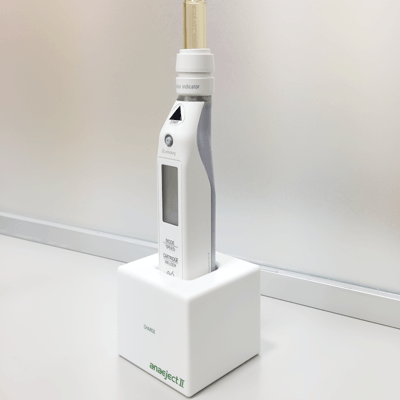

そこで使用するのがこの電動の麻酔です。

コンピューターがお薬を入れる速度を自動でコントロールし、痛くなりにくいようにしてくれます!

ちなみに癒しの音楽も流れます。